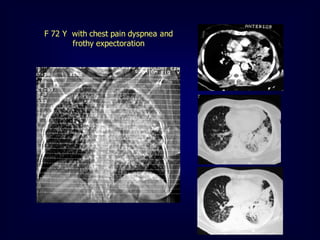

F 72 Y with chest pain dyspnea and

frothy expectoration

Alveolar proteinosis

Alveolar filling by proteinaceous material

Male : female 4:1

Possible causes:

 Idiopathic

 Occupational (silica)

 Drug- induced

 Immune compromise

Geographic distribution of areas of ground

glass opacities + thickened interlobular septa

within  crazy paving appearance

Air bronchogram is uncommon

F 72 Ywith chest pain dyspnea and frothy expectoration

Alveolar proteinosis Alveolar fillingby proteinaceous material Male : female 4:1 Possible causes:  Idiopathic  Occupational (silica)  Drug- induced  Immune compromise Geographic distribution of areas of ground glass opacities + thickened interlobular septa within  crazy paving appearance Air bronchogram is uncommon